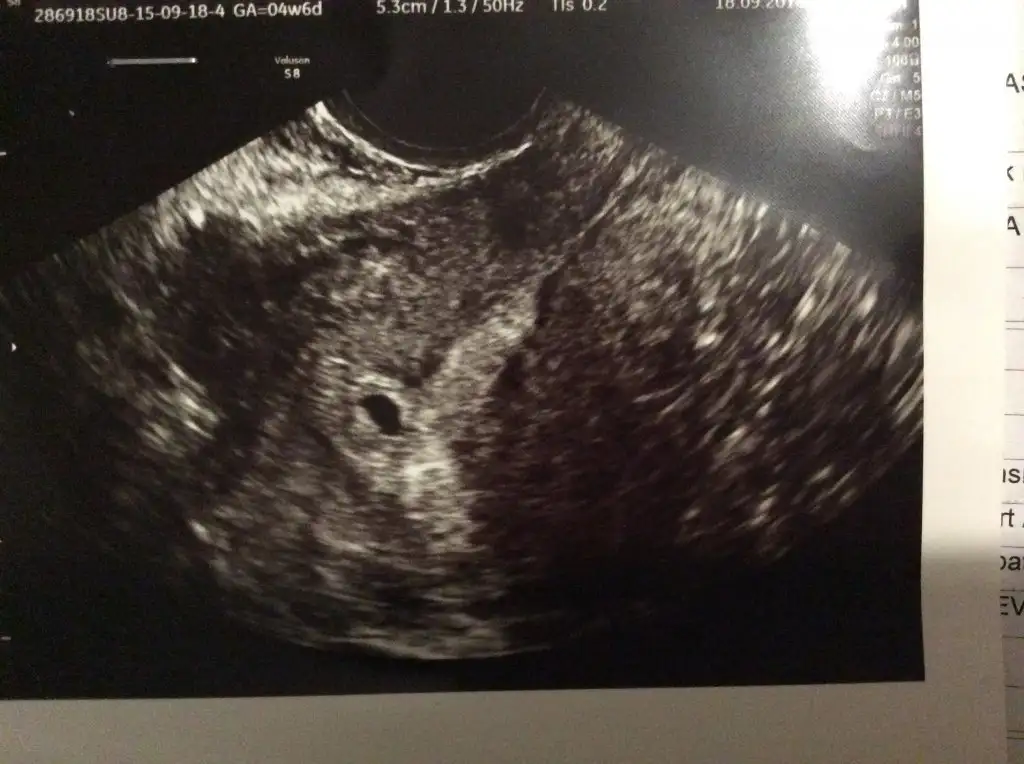

Selam kızlar. Ben de bugün hastaneye gittim. Bebeğin kesesini görebildik çok şükür

Ben de bugun kalp atışlarını duydum çok şükür hiç kulagimdan gitmiyor pıt pıt :) yalnız biz 6 hafta 5 günlük göründük ultrasonda seninki kaç haftalık göründü canım?Canım ben hiç sormadım kese boyutunu drum da hiç söylemedi zaten bugün minnak bebişi görünce herşey uçtu gitti aklımdan ultrason kağıdını bile istemeyi unuttum

Ben bugün fasulyemin kalp atıslarini dinledim. Hizli hizli pit pitcok duygunlandim. 4 mm olmus. Bugun 2. Fotografini da aldık İnsallah hepinizin böyle haberlerini aliriz.

Benim bugün vajinadan ultrasonla gözüktü kesem. 4+6 dayım. Daha önceki gebeliğimde de böyle alttan bakılması gereken durumlar olduğu için bugünde bir sıkıntı olmadı benim için.maşallah ya gözün aydın darısı başıma

benımde doktor gorememıstıBenim bugün vajinadan ultrasonla gözüktü kesem. 4+6 dayım. Daha önceki gebeliğimde de böyle alttan bakılması gereken durumlar olduğu için bugünde bir sıkıntı olmadı benim için.